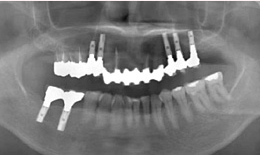

インプラント症例(23) 60歳 女性

治療方法

- 上顎

- 保存困難な歯を抜歯後、インプラントを5本埋め込んで、セラミックスクラウンを被せた

- 下顎

- インプラントを2本埋め込んで、セラミックスクラウンを被せた